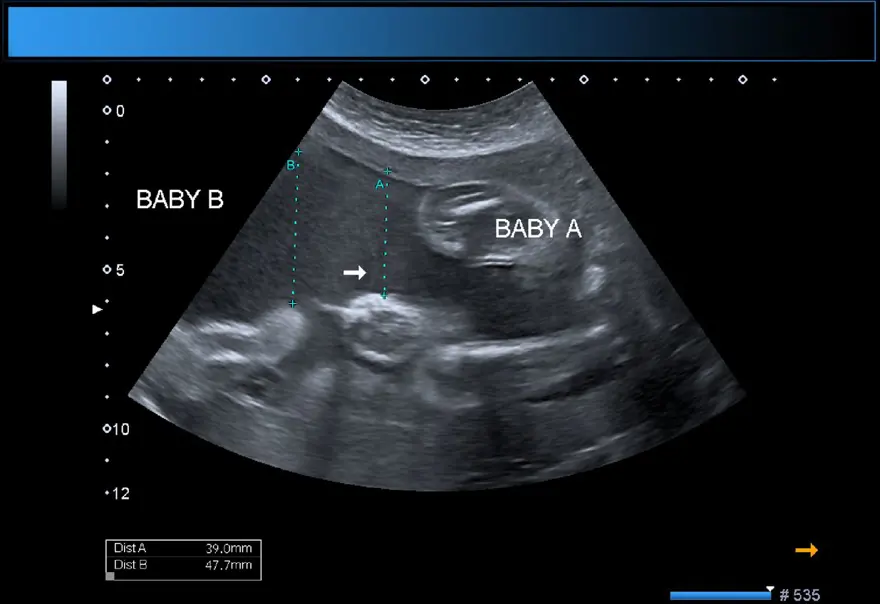

Şangay'daki doktorlar, doğmamış ikizin fetüsünün çocuğun beyninde geliştiğini tespit etti. Çalışmanın yazarları, "Motor becerilerinde gecikmesi ve genişlemiş baş çevresi olan 1 yaşındaki bir kız çocuğunda malforme olmuş monokoryonik diamniyotik ikiz olan intraventriküler fetüs içinde fetüs (fetus-in-fetu) tespit edildi." denildi.